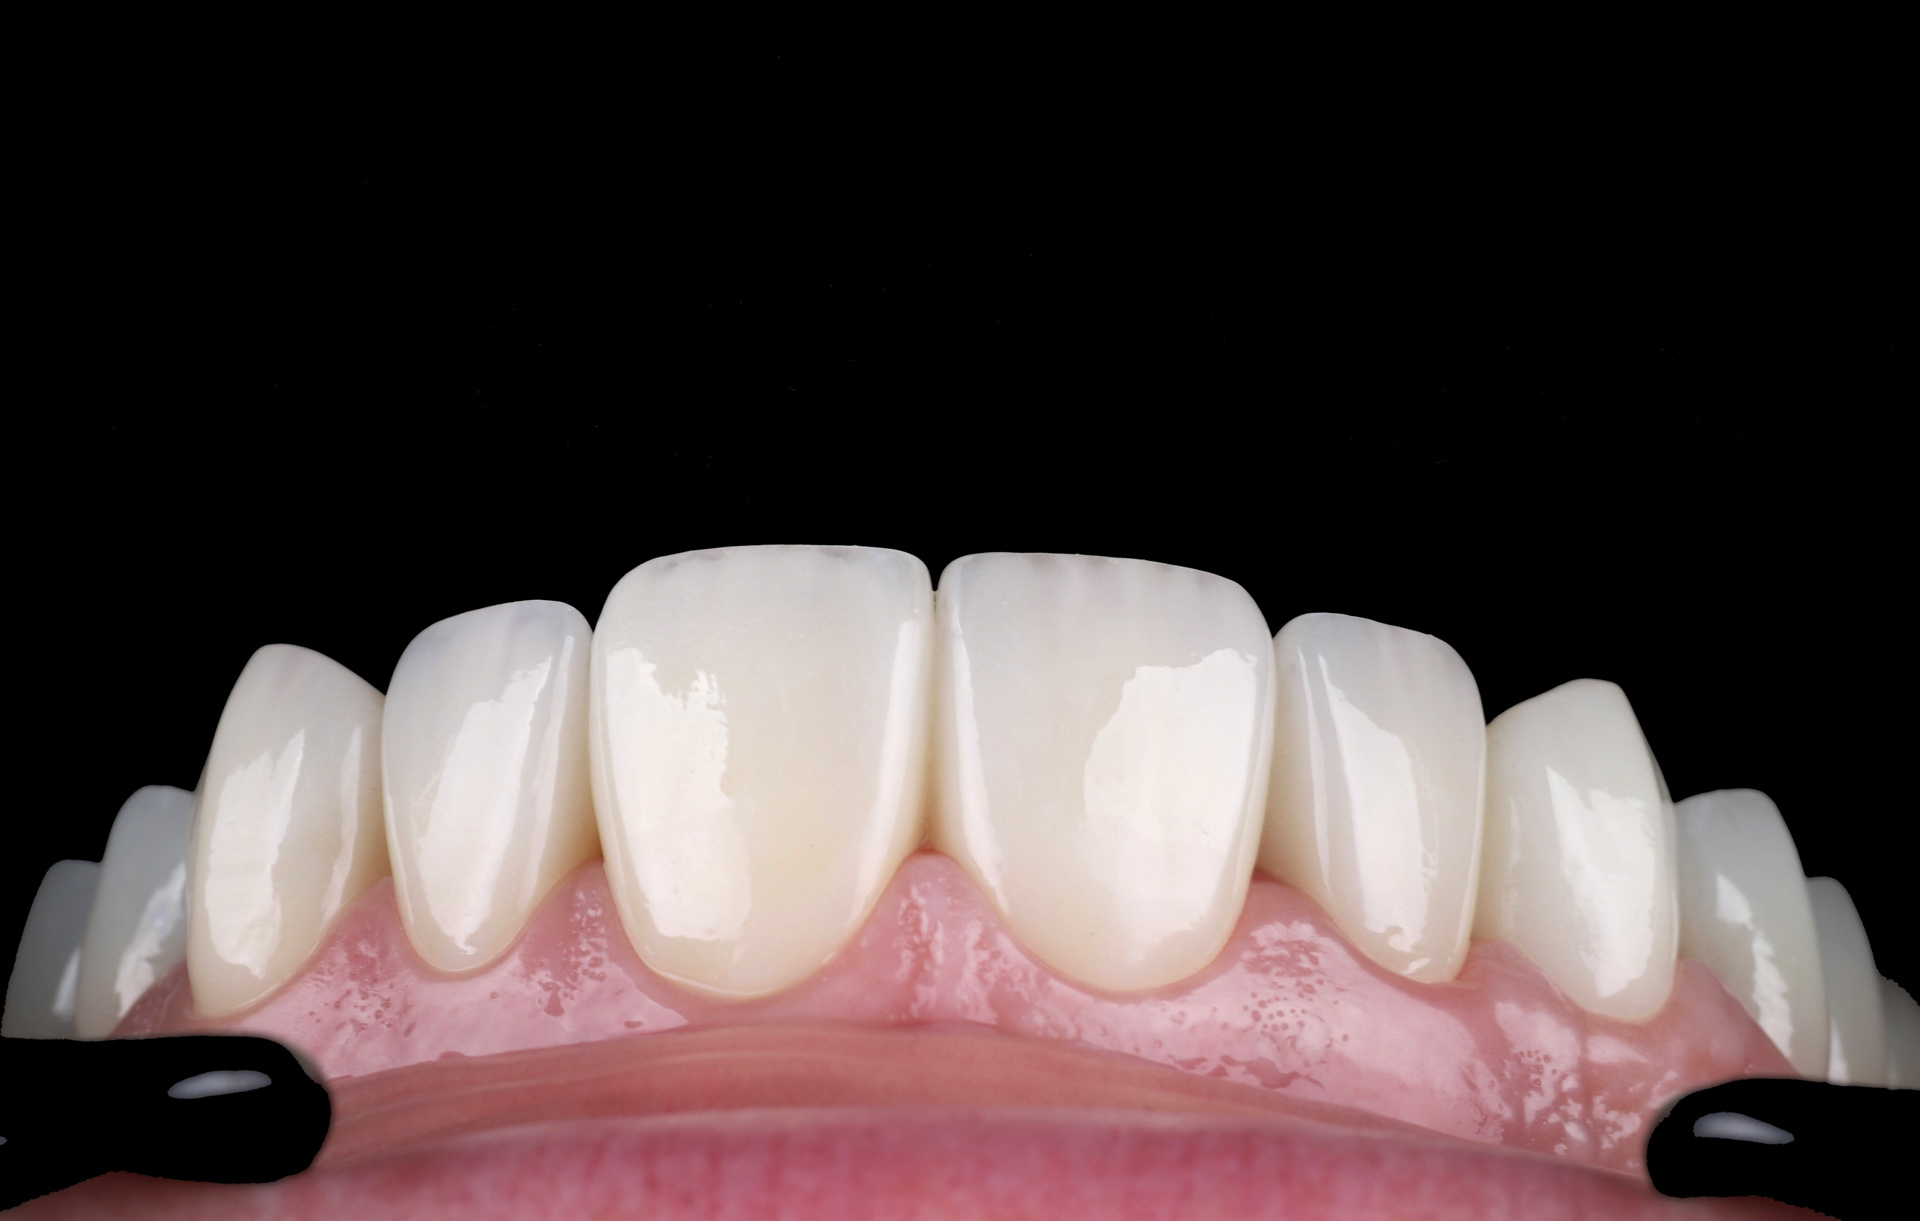

Лесі порекомендував звернутись до мене її лікуючий стоматолог з приводу корекції естетики усмішки. Після планування та обговорення всіх деталей ми встановили імплантант в естетичній зоні. Згодом змоделювали індивідуальну форму та обрали пропорції нових керамічних вінірів.

Результатом залишились задоволені всі учасники лікування,а саме технік лікар і пацієнт! Якщо бажаєте отримати такий результат – записуйтесь на консультацію.